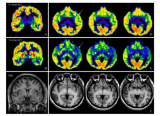

IEEE JBHI封面 | 胡战利研究员团队实现全脑区PET/MR高清成像

脑科学作为生命科学领域的重要前沿分支,其复杂性构成了科学研究中的一项重大难题。特别是如阿尔茨海默病、抑郁症、自闭症、帕金森病等神经退行性疾病和精神疾病领域,脑科学研究对于理解其神经生物学基础至关重要。结合解剖结构和功能代谢信息的一体化PET/MR设备,是目前神经系统疾病诊断和科学研究的一种重要多模态分子影像技术。然而,PET/MR扫描需要注射标准剂量的放射性示踪剂,增加了患者的辐射风险。近日,中国科学院深圳先进技术研究院... 2024-09-25 核技术核医学PET/MRI